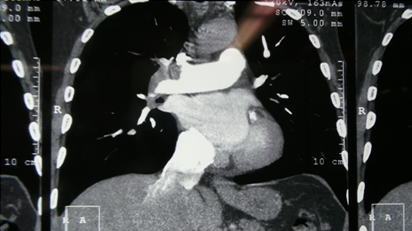

CT Pulmonary Angiography Showing Intra Pulmonary Filling defects

Filling Defects Within Pulmonary Artery